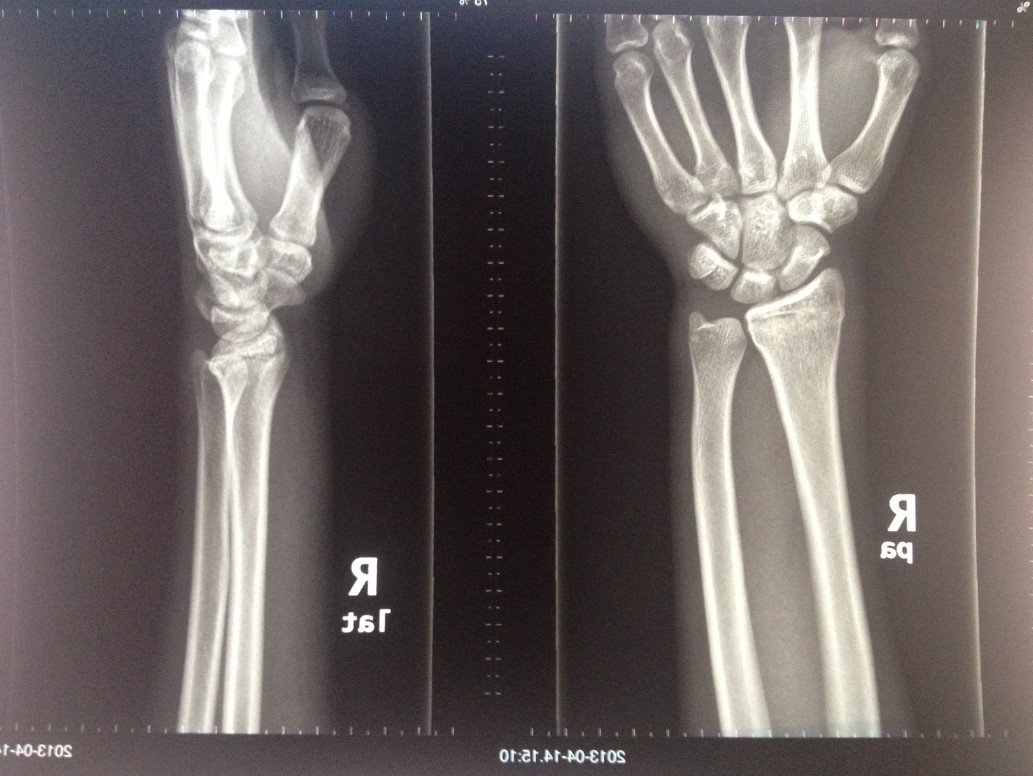

跪求懂得人士帮我看一下这个手腕片子是不是“下尺桡关节是脱位”??急!!感谢~~

这个片子还有“下尺桡关节是脱位”是吗??求确认!我这右手是摔倒时撑地弄伤的。  在医院拍x光检查结果:(右桡骨远端见横行骨折线,骨折端午明显移位或成角;余骨结构完整,未见骨折征;下尺桡关节间隙如常,桡腕关节关系可,未见脱位;玩周软组织稍肿胀。诊断:右桡骨远端横形骨折)上图。    我发到网上想了解这骨折严不严重,有热心网友说我这个片子还有“下尺桡关节是脱位”的,说医院漏诊了!是不是这么回事?望各位医生朋友懂得的朋友帮我看看,感谢!

是骨折了,在医学上叫刺刀手,不过你的不严重,复复位,敷一下药沙抗务残源应该就好,祝您早日康复战辉!

是骨折了,你是不是撞到什么????我以前也手部骨折,跟你这个很像,但是老医生帮我接回去,然后敷了两个星期的药,没有那么严重!也没有听说说的下尺桡关节是脱位。。我只能帮你这么多了,望采纳!